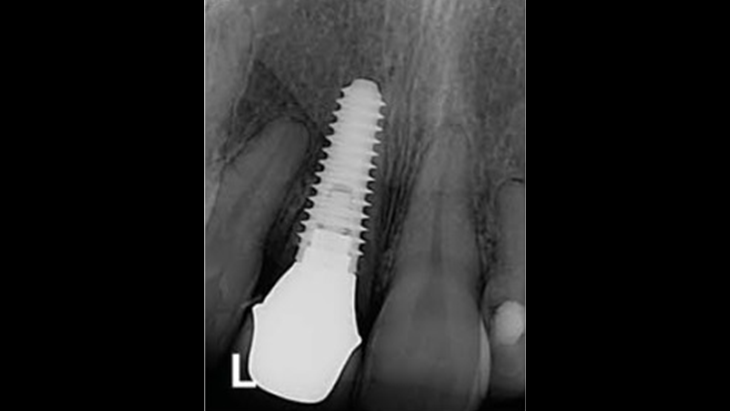

Clinical case: Bone growth in deepest thread of 8.0mm AnyRidge fixture

- Courtesy of Dr. Kwang Bum Park -

“Immediate loading of single AnyRidge implants

is a highly successful treatment modality. ”

Clinical case: Immediate post-extraction insertion of implant & immediate loading

- Courtesy of Prof. Giuseppe Luongo, Italy -

AnyRidge, immediate loading, single implant, multicenter study, maxillary anterior, Prof. Giuseppe Luongo, single replacement